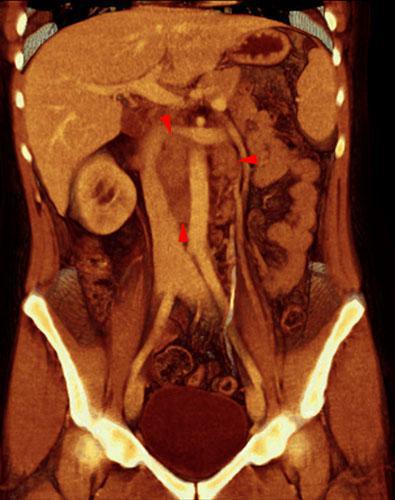

Linfoma renal secundario